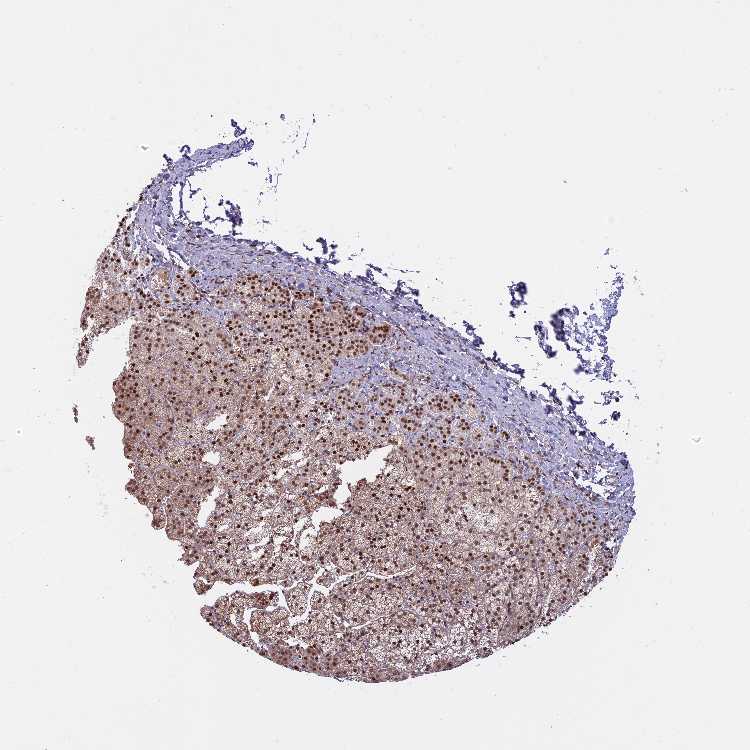

ADRENAL GLAND - Antibody stainingi

Antibody staining in the annotated cell types in the current human tissue is reported as not detected, low, medium, or high, based on conventional immunohistochemistry profiling in selected tissues. This score is based on the combination of the staining intensity and fraction of stained cells.

Each image is clickable and will lead to virtual microscopy that enables deeper exploration of all samples and also displays staining intensity scores, fraction scores and subcellular localization as well as patient and tissue information for each sample.

Antibody HPA035831Antibody CAB002669

Glandular cells MediumNot detected